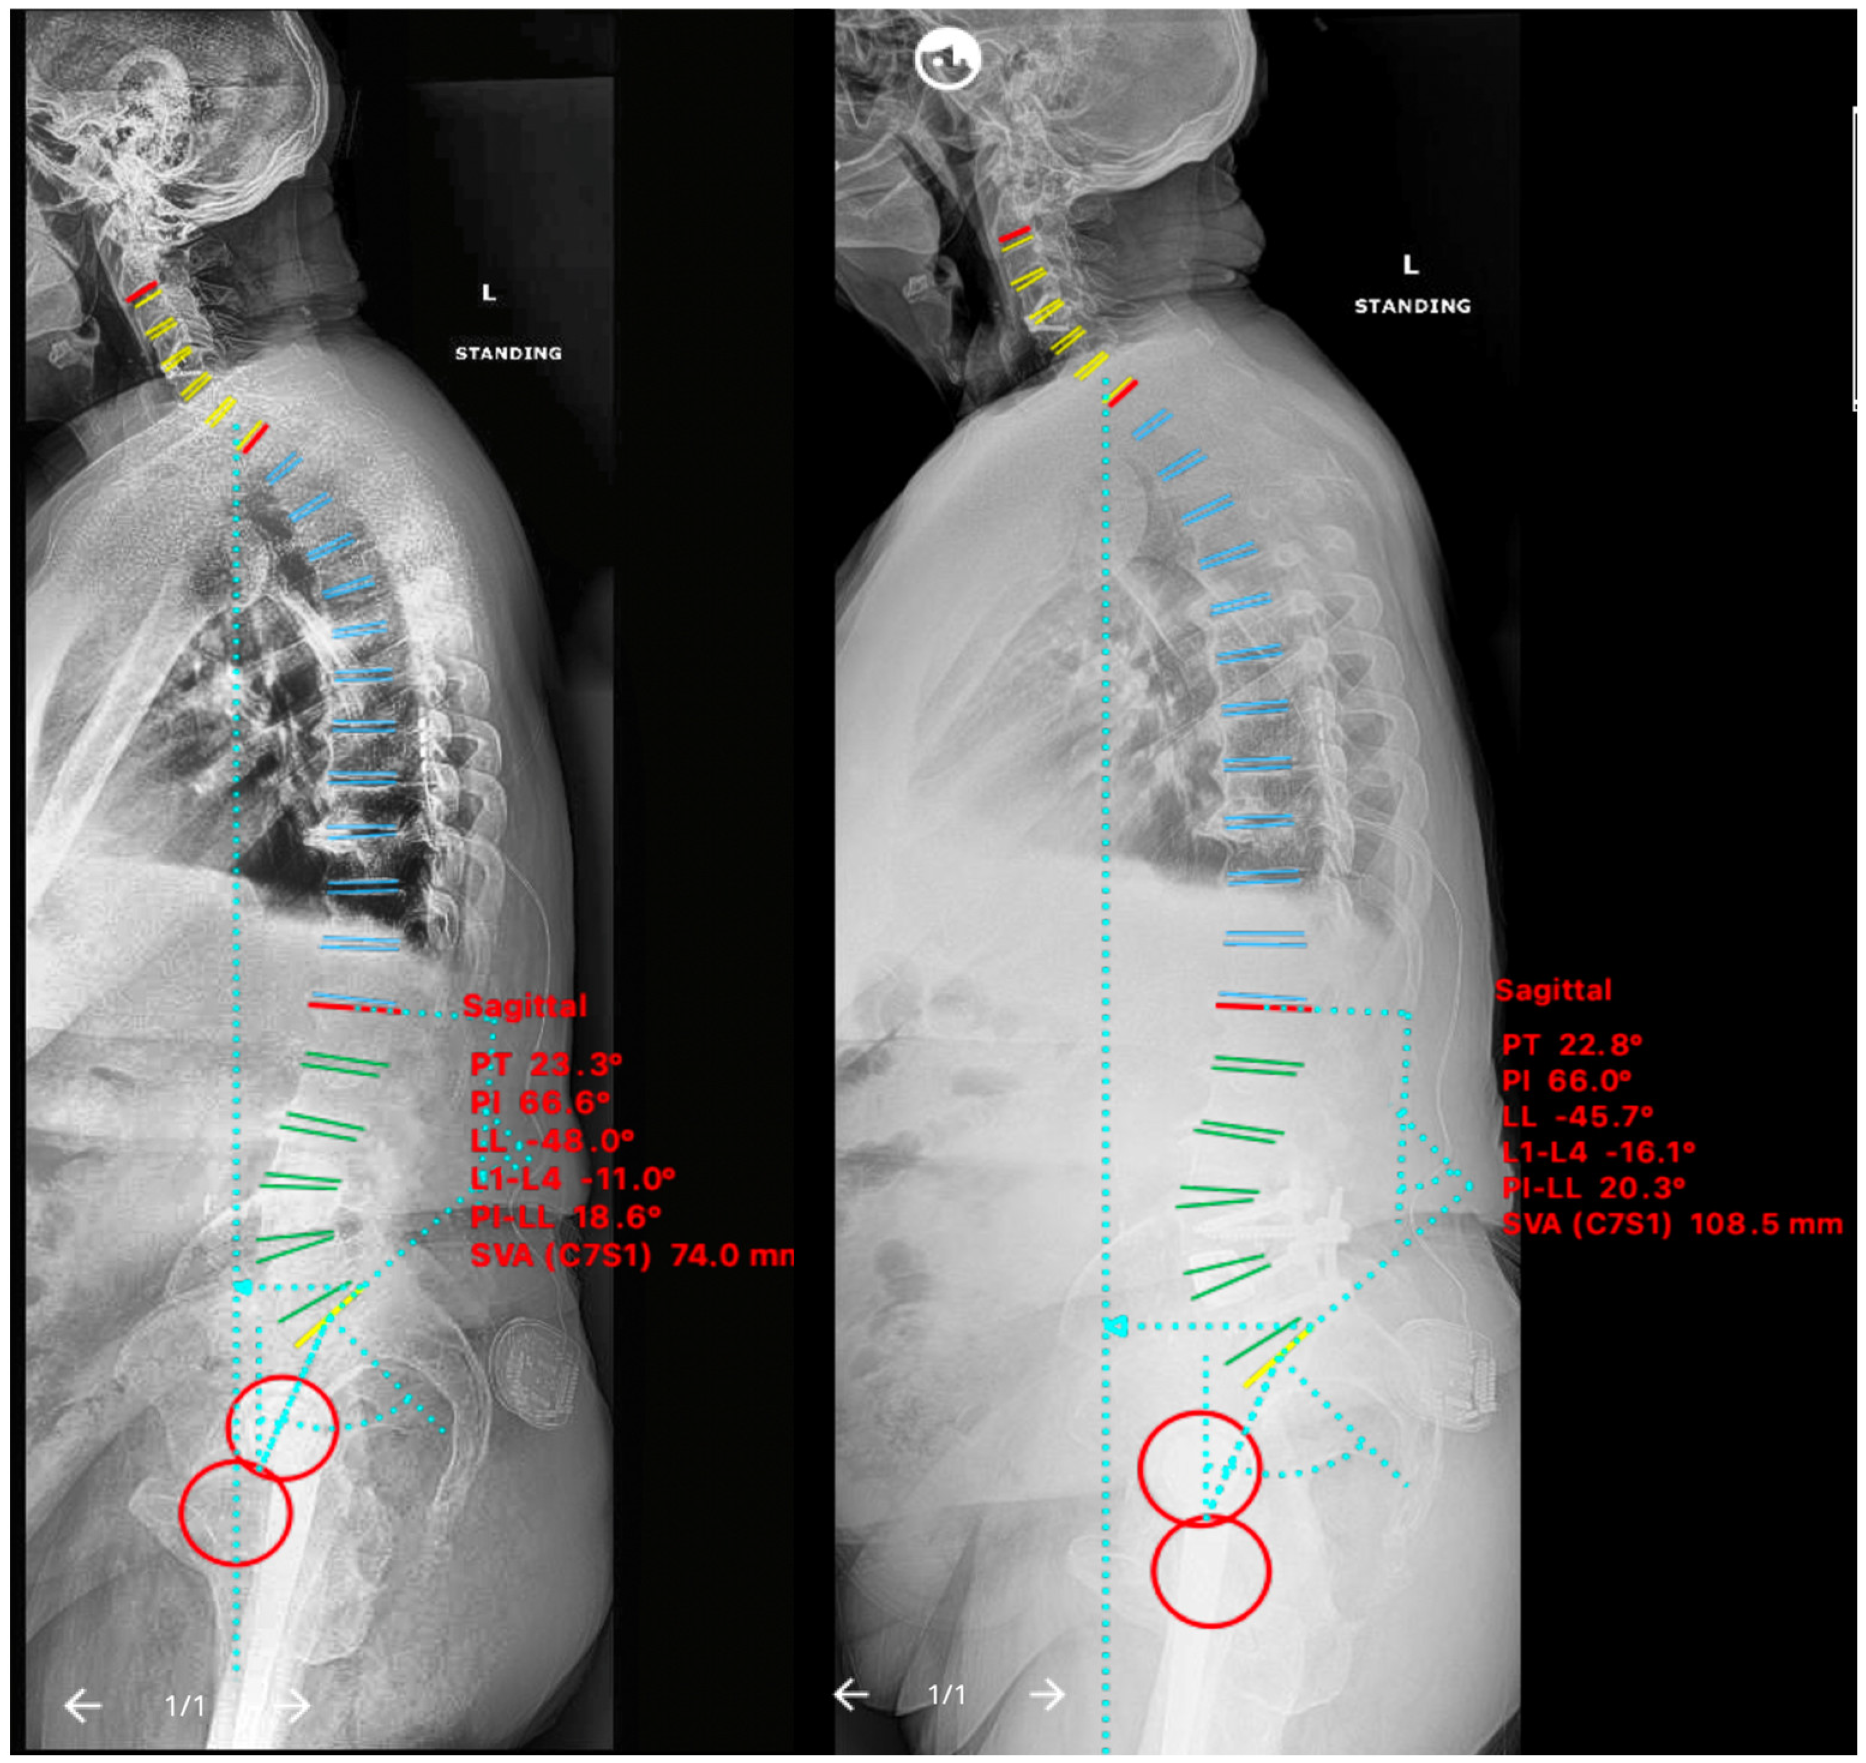

2.5.1. Case IV

2.5.2. Case V